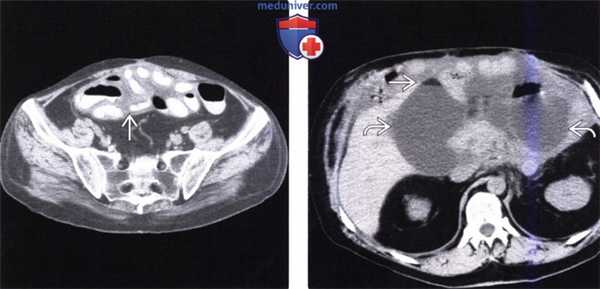

(Слева) На аксиальной КТ у мужчины 54 лет со схваткообразной болью в животе и приливами визуализируются гиперваскулярные метастазы в печени и по брюшине.

(Справа) На корональной КТ у этого же пациента визуализируется гиперваскулярное образование в терминальных отделах подвздошной кишки (первичная опухоль) в сочетании с метастазами в брыжейку с наличием десмопластических изменений в брыжейке подвздошной кишки. Эти клинические и лучевые признаки являются классическими изменениями при карциноидном синдроме.